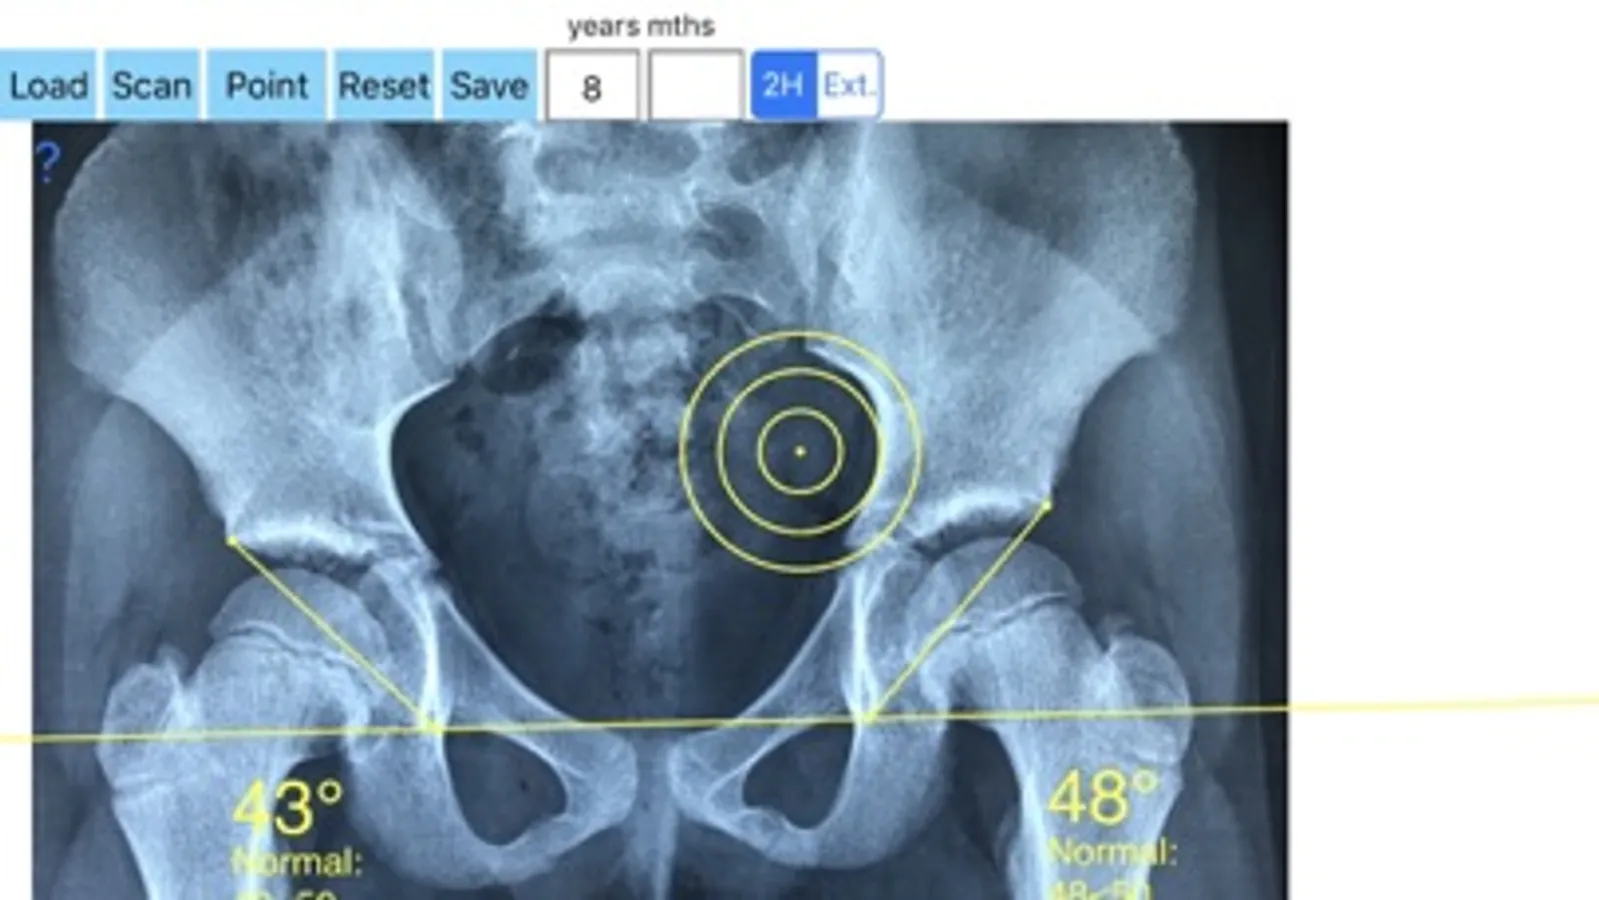

-Securely import medical images directly from the camera or stored photos

-Offers a very convenient way to determine the most accurate possibly lines in order to measure the angles. By the aid of a circular transparent template, the points of interest are marked accurately. The automatically formed lines, drawn between points, measure automatically the angles of interest. The results are printed in degrees. By inputing the age, of the patient in the App, the measured angle is compared with values from normal reference database according to patient age. In case the measured angle is beyond the normal range for that age, the hips are categorised as borderline dysplastic or dysplastic.

The app is a handy tool for an orthopaedic surgeon, radiologist, medical student or resident who wants objectively monitor and determine the severity of dysplasia of the hip. The build-in comparison feature with the normal reference values according to patient age may help decide what could be considered normal or borderline dysplastic or dysplastic. The app is not a simple goniometer, is an enhanced product which offers the ability to compare all the input data with medical reference database. The results are printed on the screen and the hips are categorised as normal or dysplastic according to the AA angle measures respectively. This feature it is particular useful especially in clinical settings where you need a quick results without losing time in looking for reference data according to age variations in huge textbooks.